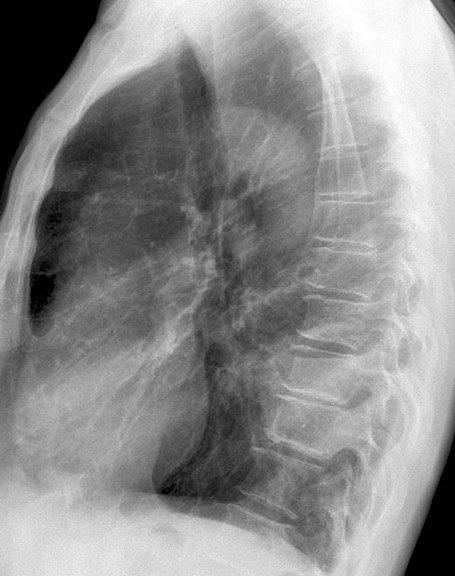

Case 16 Pneumonia Lat